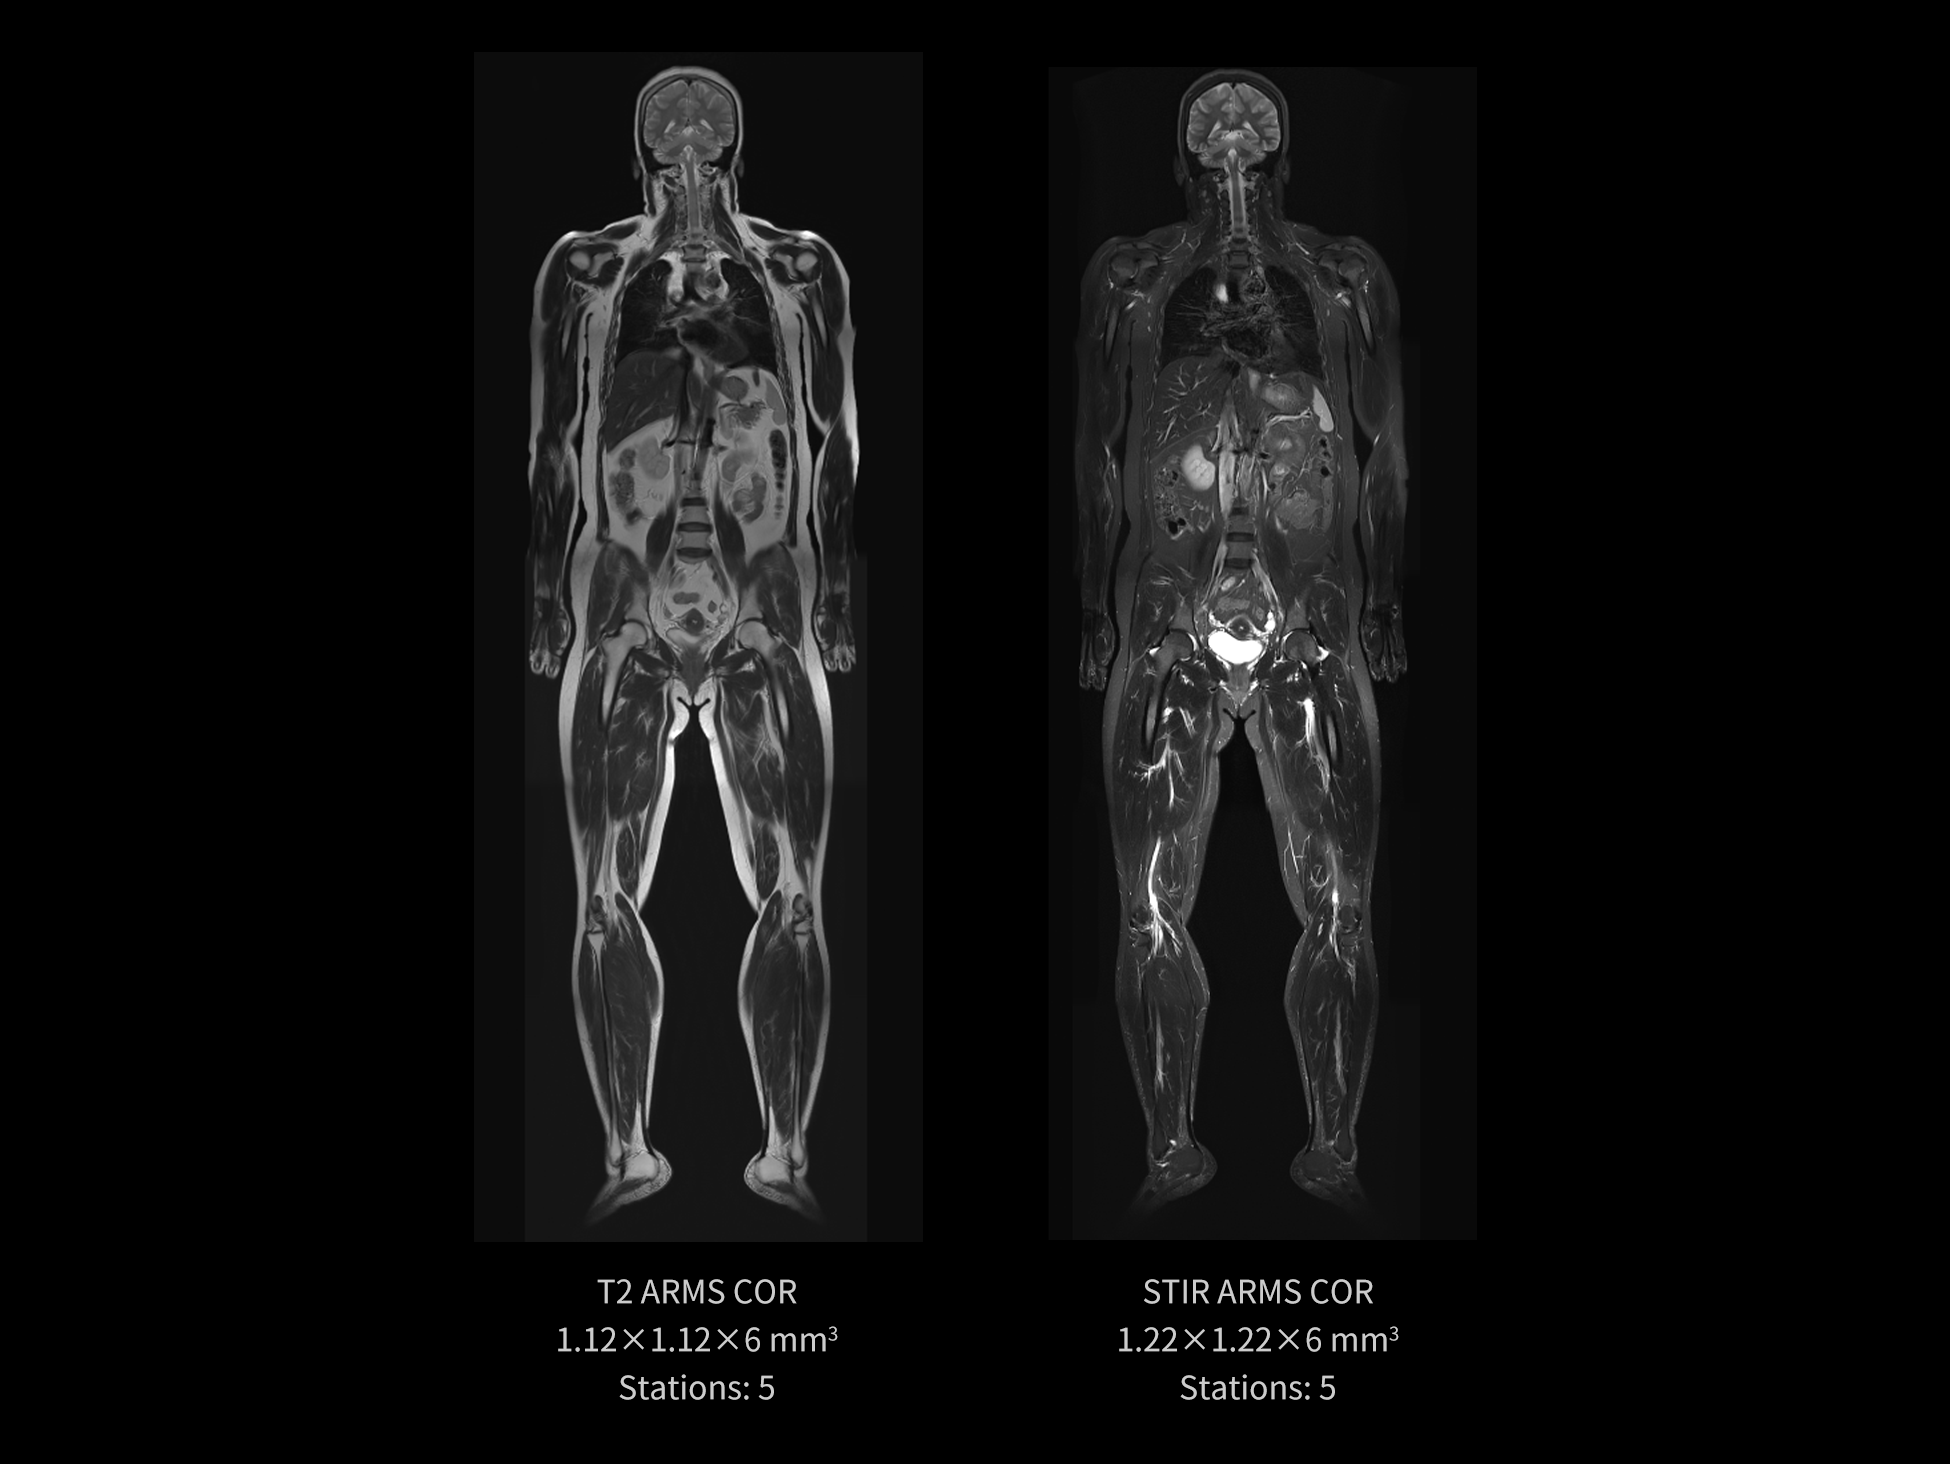

Built on the excellent magnet homogeneity and the application of EasyPlan, uMR 670 enables large-scale imaging of the whole body in structural detail.

Images courtesy of United Imaging.